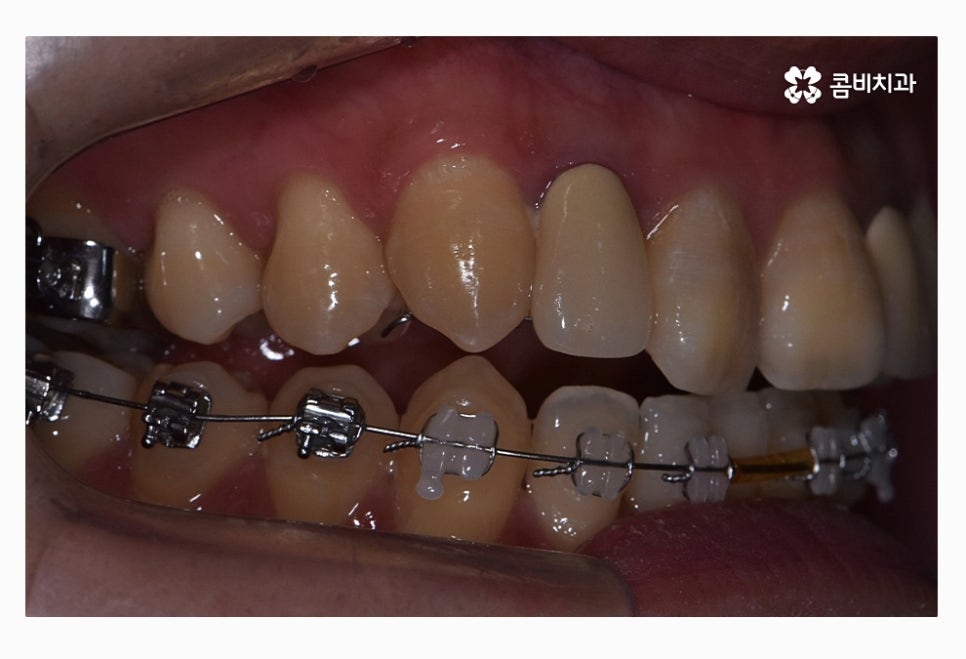

콤비교정이 시작된 후 사진이며 윗니는 교정 장치가 눈에 띄지

않는다는 점이 콤비교정의 특징이라고 할 수 있는데요.

평소에 입을 크게 벌리거나 크게 웃지 않는다면

외부에 교정을 하고 있다는 사실에 대해

거의 티가 나지 않을 정도로 심미성이 우수한 치료라고 할 수 있어요

위 사진을 다시 한번 자세히 보면 윗니는 치아의 안쪽에

교정 장치가 부착이 되어 있는 모습이며

아랫니는 일반적인 교정 방법으로 장치가 부착되어 있어요.